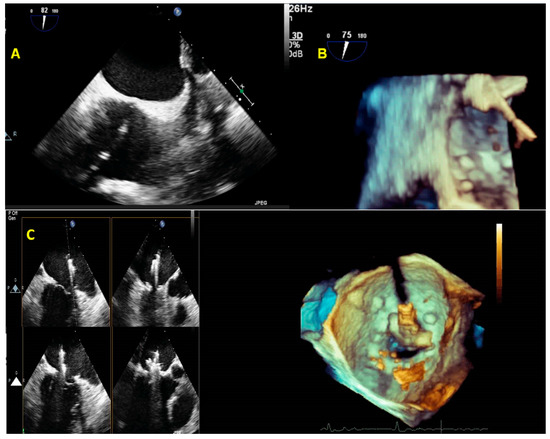

2.4. Post-Processing (Multiplanar Reconstruction and Cropping)